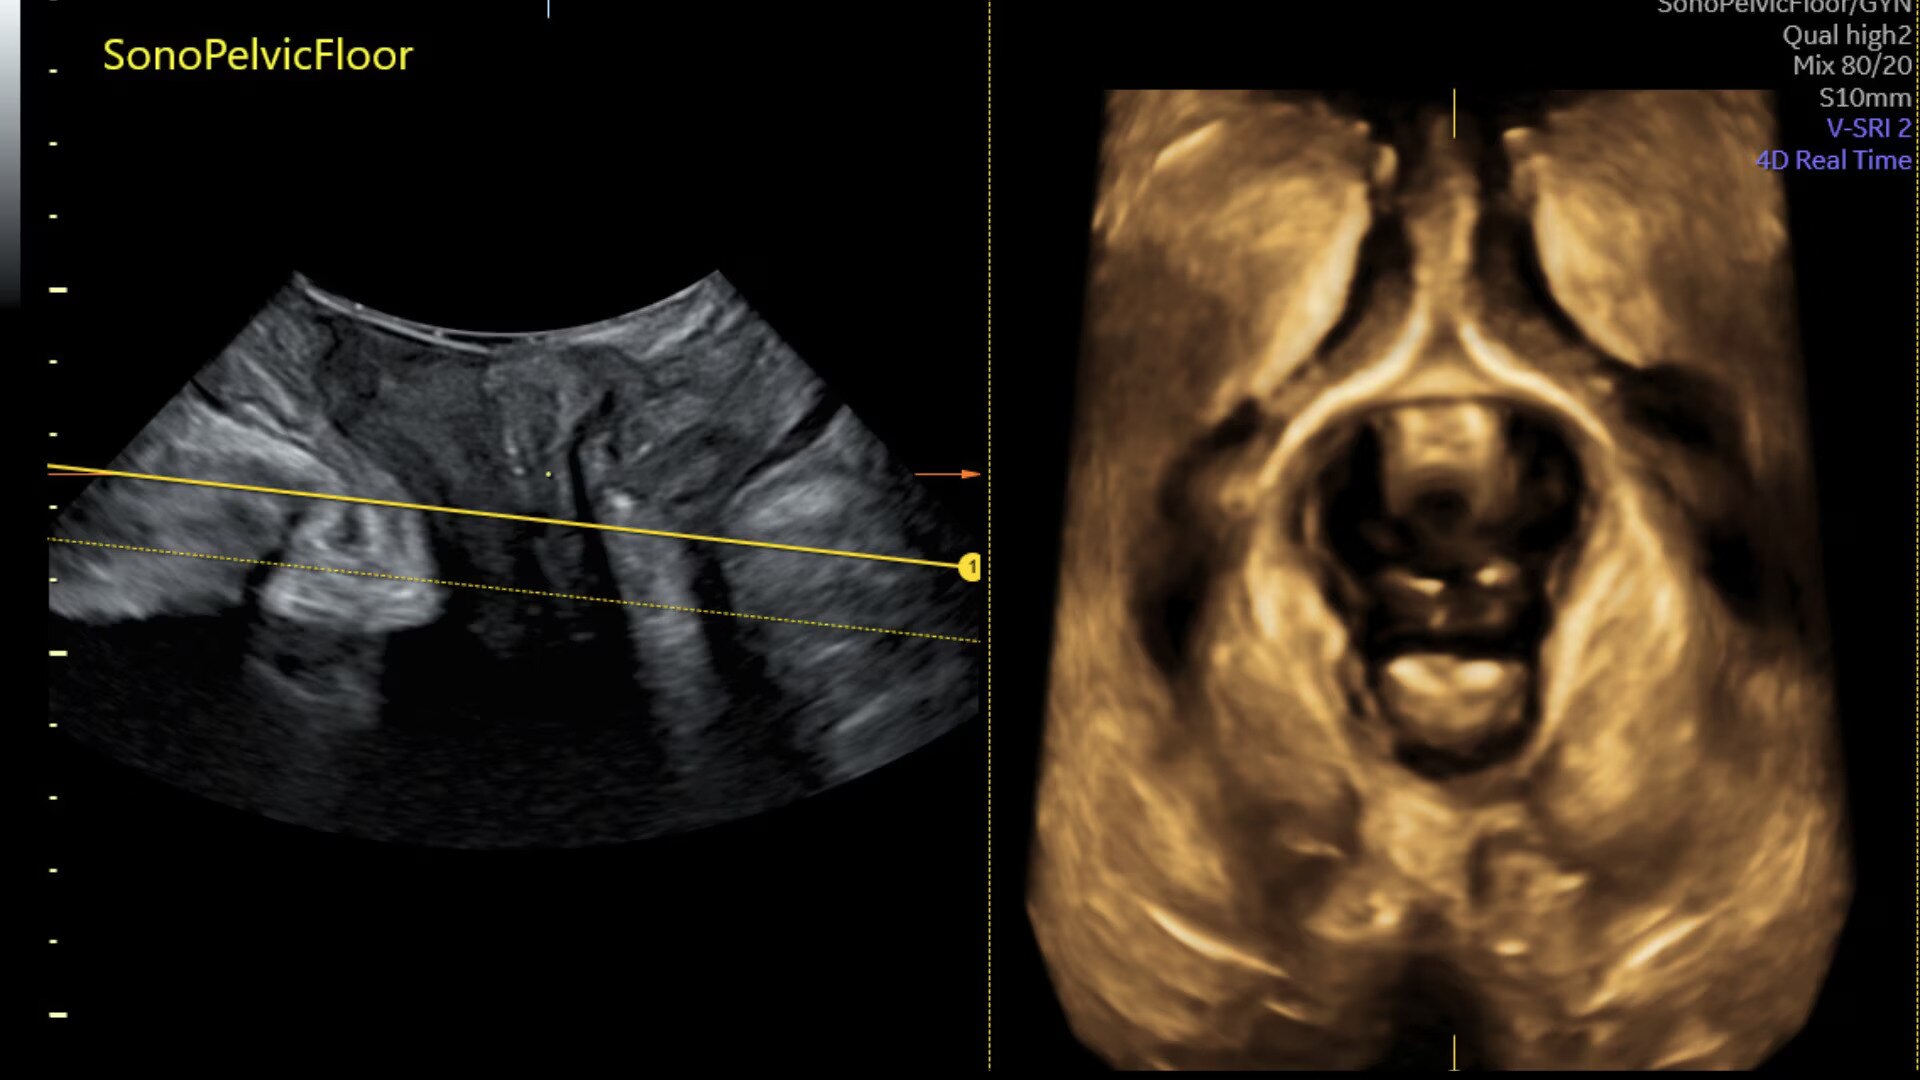

Assess pelvic floor anatomy using guided workflow & AI

Using a guided workflow and AI, SonoPelvicFloor:

• removed exam complexity by automating plane alignment and measurements

• can reduce keystrokes by up to 75% and offer users a time savings of up to 80%